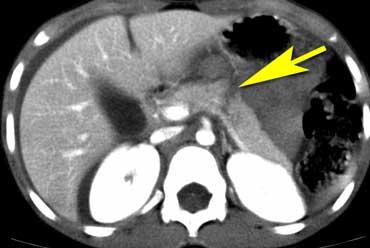

Hình ảnh

CT cho thấy hình ảnh rách tụy trong trường hợp bạo hành trẻ em.

Rách gan trong trường hợp bạo hành trẻ em